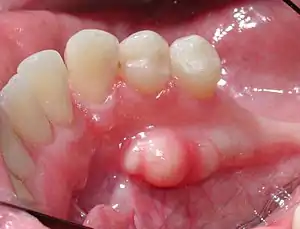

Mandibular torus in premolar area

Torus mandibularis is a bony growth in the mandible along the surface nearest to the tongue. Mandibular tori are usually present near the premolars and above the location of the mylohyoid muscle's attachment to the mandible.[1] In 90% of cases, there is a torus on both the left and right sides.